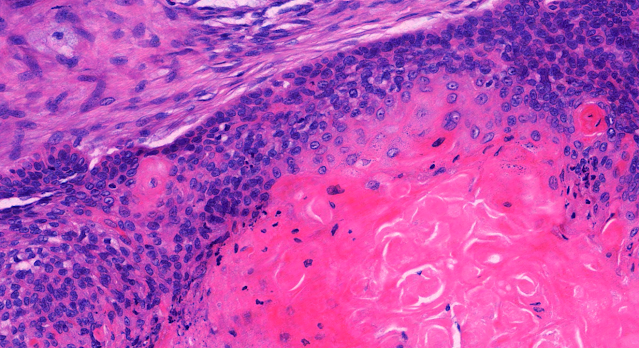

Dermatopathology Case 262 Get link Facebook X Pinterest Email Other Apps September 07, 2022 A 56 year old women with a slowly enlarging, painful scalp nodule. Answer Get link Facebook X Pinterest Email Other Apps Comments